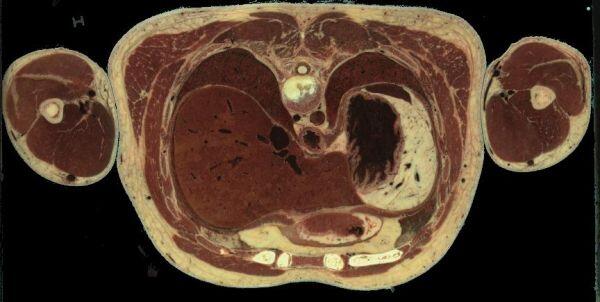

à 493 mm du sommet du crane, le coeur n'est plus visible mais les poumons gauche et droit se trouvent derrière foie et estomac :